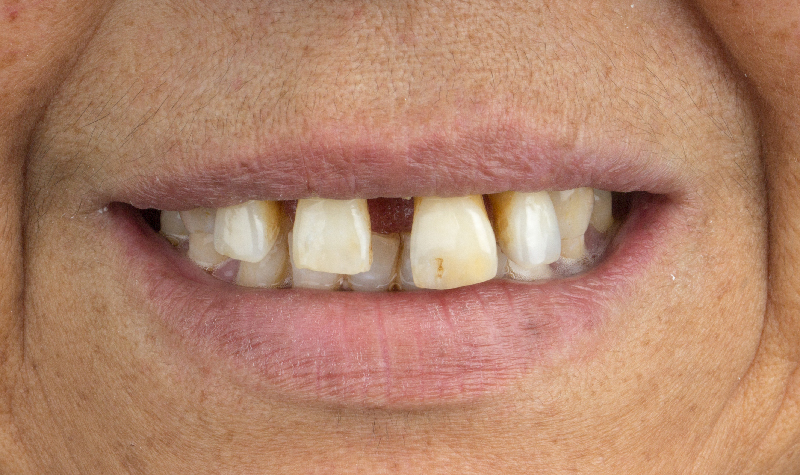

Diseño de Sonrisa Digital con carillas de cerámicas.